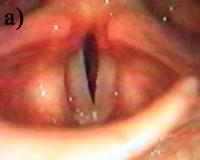

• Ларингоскопия. Объективная эндоскопическая картина характеризуется гиперемией, утолщением, припухлостью голосовых складок, усилением секреции слизи. Во время фонации складки не закрываются, так называемые «Мутационный треугольник» или овал.

При патологическом характере мутации под влиянием вышеперечисленных причин нарушается согласованная деятельность внутренних и внешних мышц гортани. Голосовые связки попеременно вибрируют, не смыкаются, образуя треугольную щель. Суставные и лицевые мышцы напряжены. Возникает несоответствие дыхания и фонации, что приводит к нарушению формирования голоса мутационным типом дисфонии.